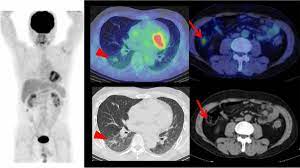

F-Conal FDG PET Scan near me